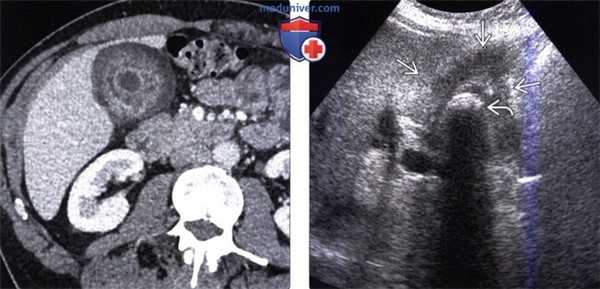

(Слева) На рисунке показан рак желчного пузыря в виде объемного образования в ограниченном участке его стенки, прорастающего в печень и обусловливающего обструкцию общего печеночного протока. В просвете желчного пузыря видны множественные конкременты.

(Справа) На корональной КТ с контрастным усилением визуализируется мягкотканное объемное образование в стенке желчного пузыря, распространяющееся кверху, прорастающее в печень и вызывающее поражение структур ворот печени. Обратите внимание на множественные камни — известный фактор риска рака желчного пузыря. (Слева) На аксиальной КТ с контрастным усилением в желчном пузыре визуализируется полиповидное образование большого размера, накапливающее контраст (рак желчного пузыря). Такие полиповидные образования составляют около 20% всех вариантов рака желчного пузыря, обнаруживаемого на КТ.

(Справа) На сонограмме визуализируется мягкотканное объемное образование (карцинома), заполняющее дно желчного пузыря. Обратите внимание на интактную эхогенную стенку желчного пузыря? отделяющую опухоль от печени, что позволяет предположить отсутствие инвазии печени.